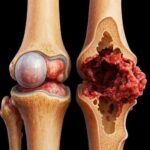

El cáncer de hueso se origina cuando las células óseas comienzan a crecer de manera incontrolada, formando un tumor maligno que destruye el tejido sano. A diferencia de los tumores benignos, que no se diseminan, los tumores cancerosos tienen la capacidad de invadir tejidos cercanos y propagarse a otras partes del cuerpo.

Es fundamental entender que existen distintos tipos de cáncer de hueso, cada uno con sus propias características y patrones de desarrollo. La diversidad de estas afecciones hace que el diagnóstico y el tratamiento sean un proceso muy específico y personalizado.

Los cánceres de hueso primarios son aquellos que se originan directamente en el hueso, y entre los más conocidos se encuentran el osteosarcoma, el condrosarcoma y el sarcoma de Ewing. Cada uno de estos tiene características patológicas y pronósticos distintos que guían las decisiones terapéuticas.

El osteosarcoma se desarrolla a partir de las células óseas inmaduras, el condrosarcoma en el cartílago, y el sarcoma de Ewing en el tejido nervioso primitivo que a menudo se encuentra en el hueso. Conocer estas distinciones es crucial para un diagnóstico preciso y un plan de tratamiento efectivo.

El cáncer primario de hueso, aunque raro, se caracteriza por su origen directo en el tejido óseo. Sus células tienen las características del hueso, cartílago o tejido conectivo, y su tratamiento se centra específicamente en erradicar estas células malignas directamente del esqueleto.

Los principales tipos, como el osteosarcoma y el sarcoma de Ewing, tienen patrones de crecimiento y localizaciones preferidas. Por ejemplo, el osteosarcoma a menudo afecta los huesos largos de los brazos y las piernas, especialmente alrededor de la rodilla.